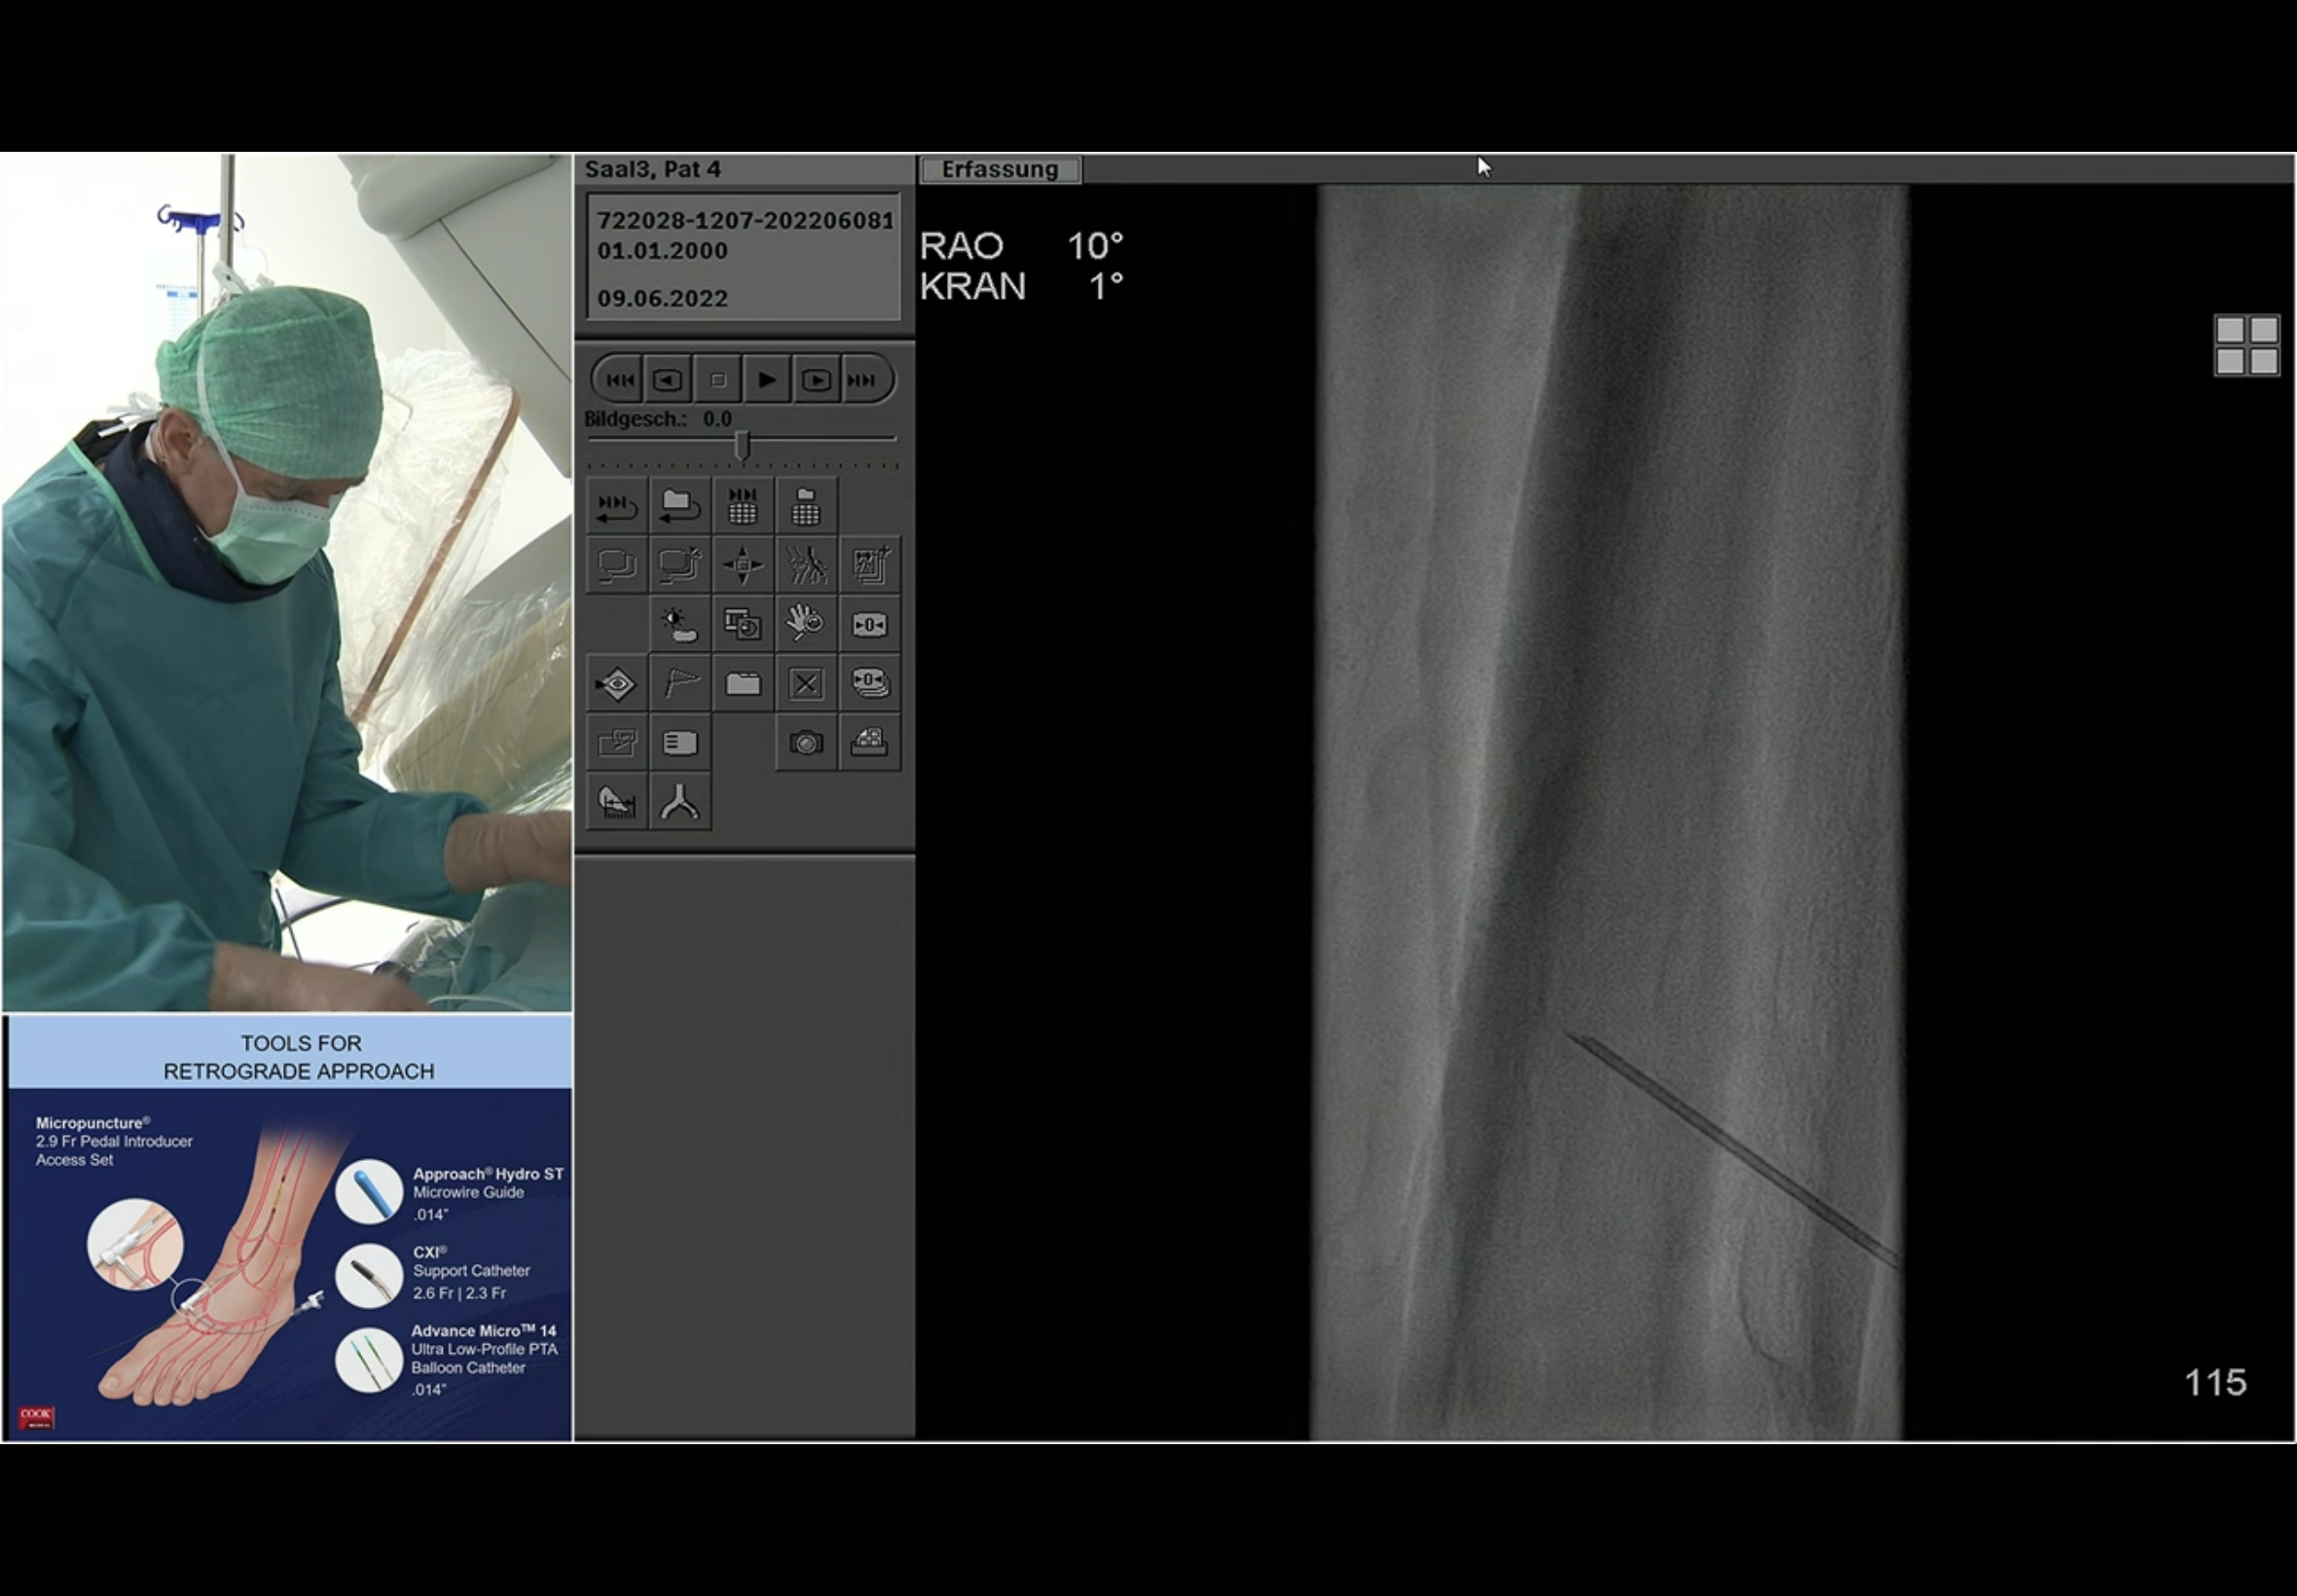

Fluoro roadmap guided puncture of the PeA. The seen vessel here is the PTA. Andrej emphasises that needle path should be parallel to the target vessel. He states that the approach to the vessel is “anterior”. The C-arm looks to be in an ipsi oblique - this is the left leg and the angle is LAO 29 on the image just before the magnified view with the needle; that is the impression I had at the time too. He then reverts to a contralat oblique RAO view to corroborate needle position and entry and then continues to work in that view.

He does the next DSA to confirm for certain that he is indeed in the PeA and not the PeV; the PeA is seen outlined lightly but certainly overlying the wire coming up from below.

The wire going up the PeA from below first turns laterally out into a collateral; then it turns medially and Andrej susses that it may in fact have gone into the PTA origin.